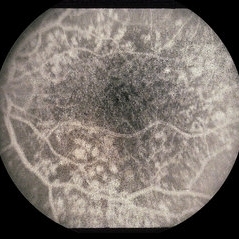

ARMD

Aug 7 2013 by H. Michael Lambert, MD

ARMD.